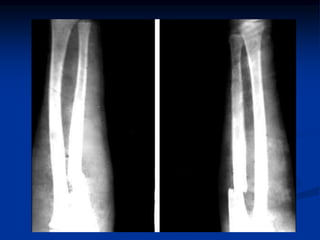

Fractura de los Huesos del

Antebrazo

 Una fractura en el antebrazo es la ruptura de uno o

ambos huesos del antebrazo.

 Generalmente son causadas por un traumatismo en

el hueso. Por ejemplo:

1.-Caer sobre un brazo extendido

2.-Caer directamente sobre el antebrazo

3.-Golpe directo en el antebrazo

4.-Doblar el brazo más allá del rango normal de

movimiento del codo

Tratamiento

 El tratamiento depende de la gravedad de

la lesión, aunque generalmente incluye:

 Reducción manual o quirúrgica.

 Diversos aparatos usados para sostener el

hueso en su lugar mientras sana, por

ejemplo:

 Una férula o tablilla (se puede usar con o

sin cirugía).

 Una placa de metal con tornillos

(requiere cirugía).

 Solo tornillos (requieren de cirugía).